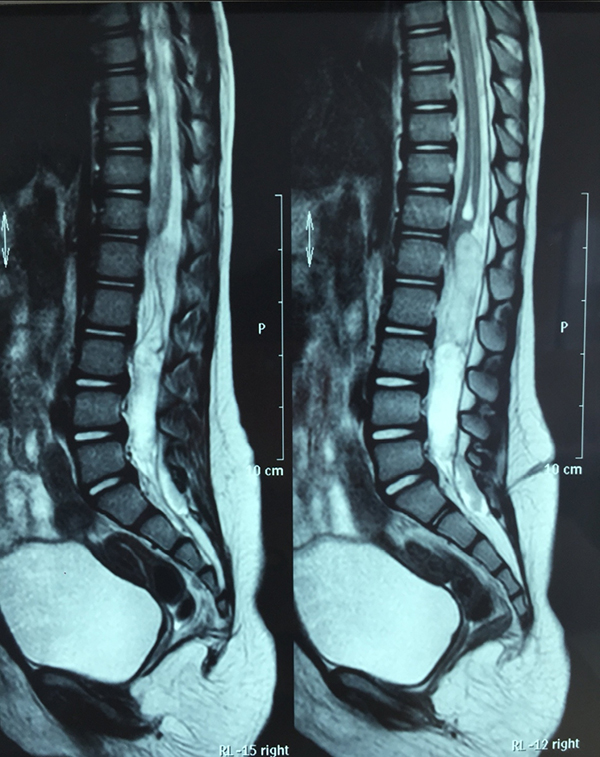

核磁共振显示瘘管及椎管内的囊肿。